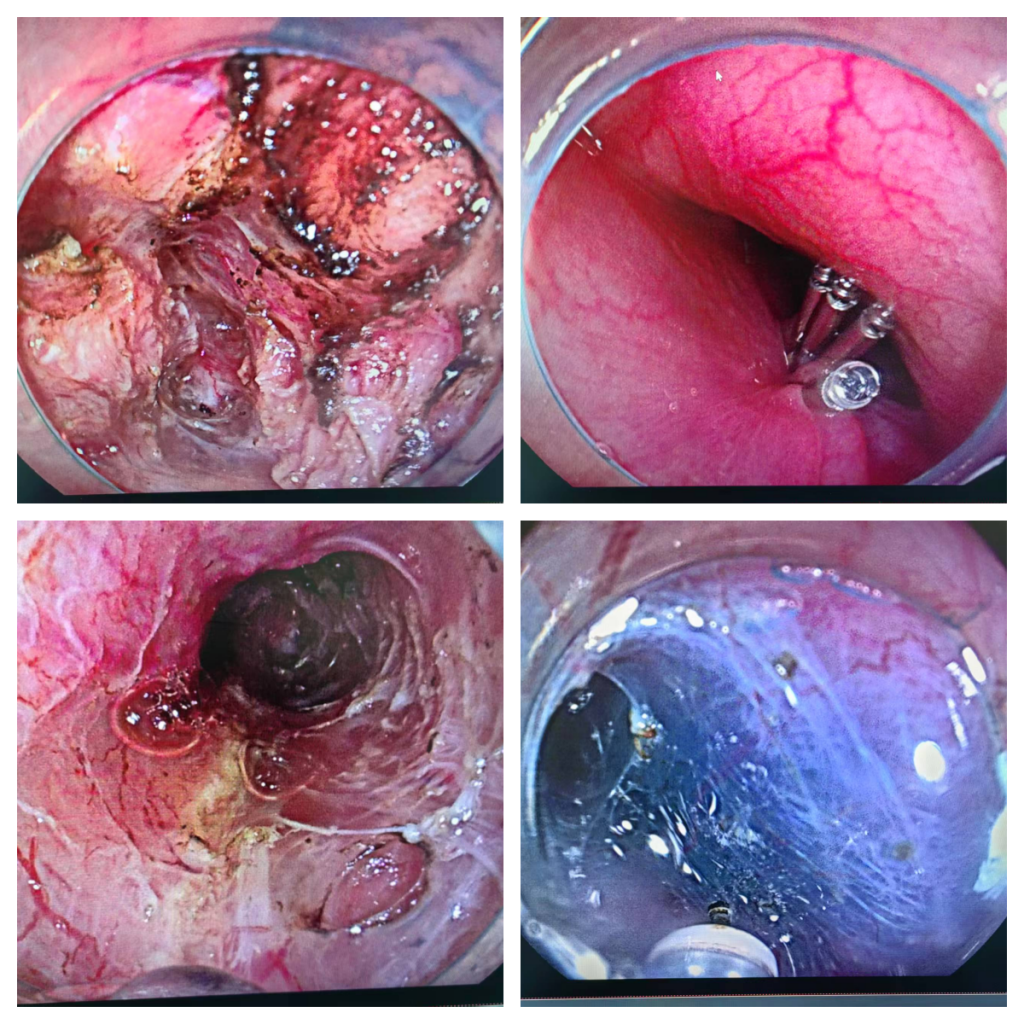

今年1月下旬,在患者及家属知情同意后,麻醉科团队密切配合,由张华宝主任医师带领指导内镜手术团队,谭巧玫副主任医师经过1个多小时的努力,成功为陈女士完成POME手术。术后第二天陈女士可以流质饮食,长期困扰她的吞咽困难症状消失,Eckardt评分0分。复查食道吞碘造影提示造影剂顺利通过贲门进入胃内,恢复良好,目前已康复出院。

关于POME手术

经口内镜下肌切开术(peroral endoscopic myotomy , POEM )是一种通过隧道内镜技术进行肌切开的内镜微创技术,2008 年被首次应用于贲门失弛缓症的临床治疗,取得较好疗效,目前已成为治疗贲门失弛缓症的优选。该技术是通过建立“隧道”的方式,在食管黏膜下层建立新通路,并在内镜下切开食管周围环形肌肉,以达到松解痉挛的环形肌,实现经口进食的目的。(文/谭巧玫 消化内科)